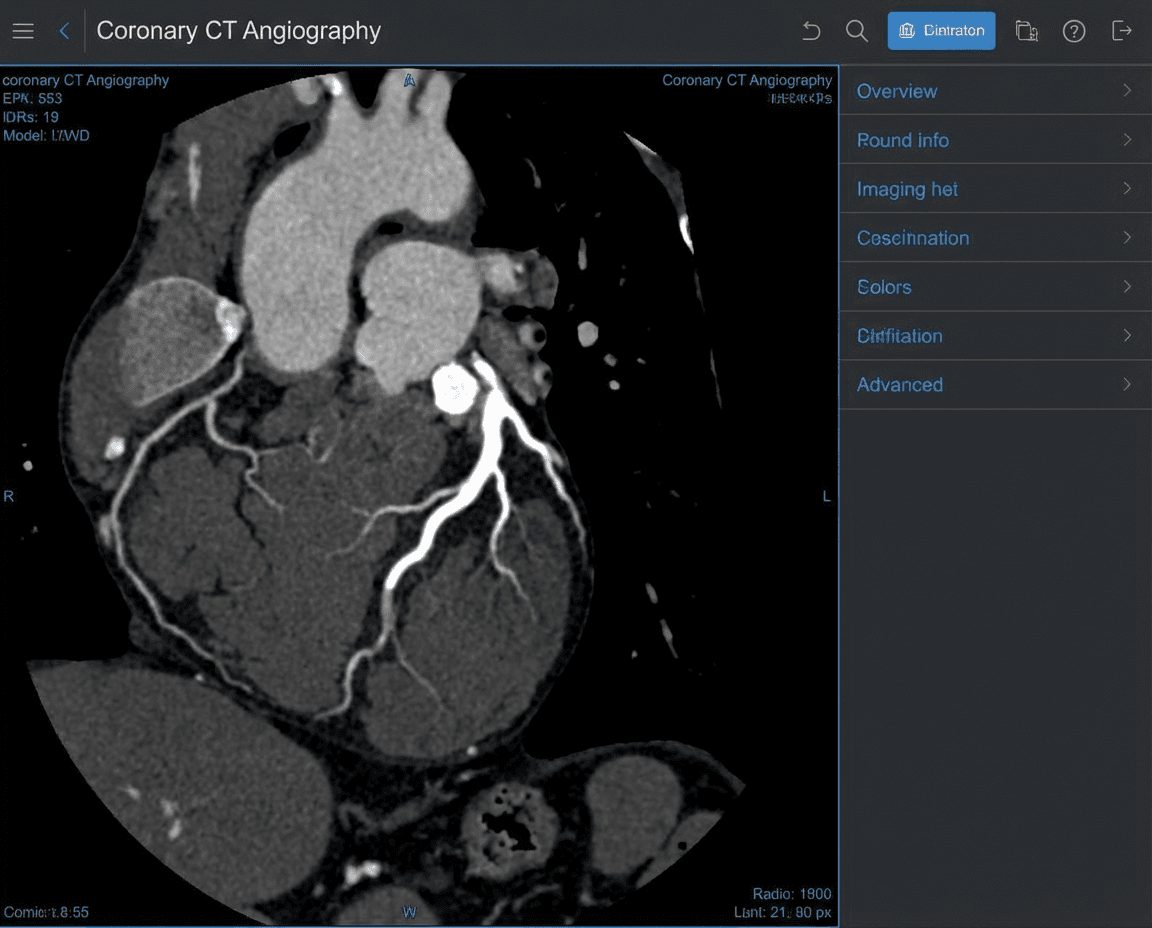

Cardiac CT

Cardiac CT (Computed Tomography) provides high-resolution, three-dimensional images of the heart and coronary arteries. This advanced imaging technique allows for non-invasive assessment of coronary artery disease, calcium scoring, and evaluation of cardiac structure and function.

Our cardiac CT specialists use cutting-edge multi-slice CT technology to detect blockages, assess plaque buildup, and provide detailed anatomical information that guides treatment decisions with minimal patient discomfort.